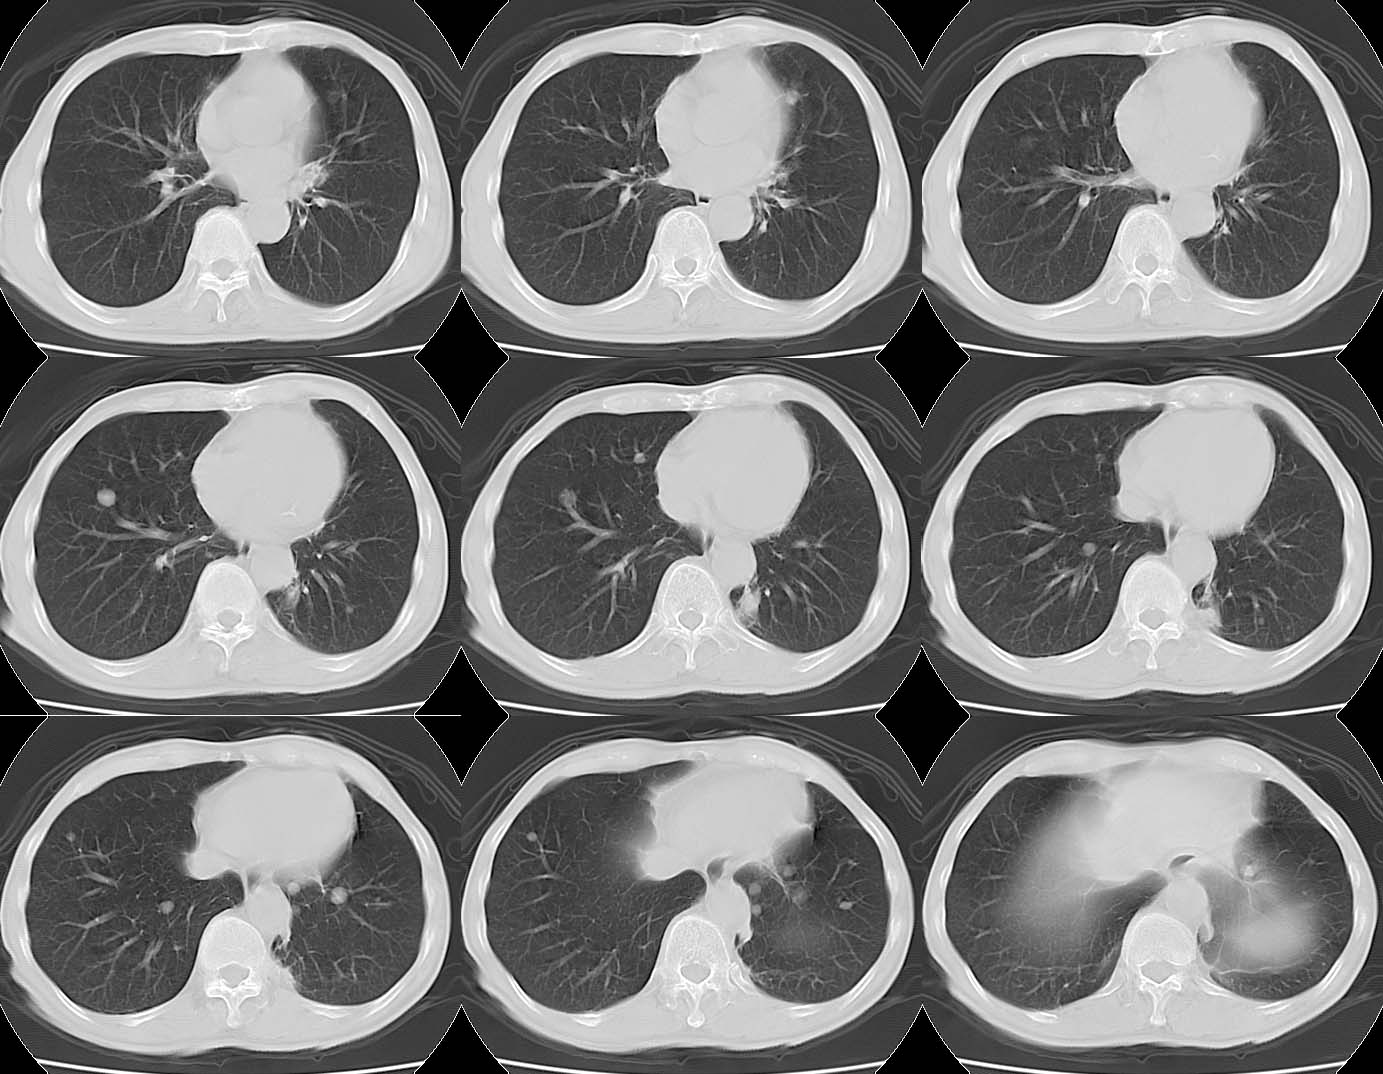

Lung Cancer: Adenocarcinoma:"High-speed screening mode."

8mmx4, Pitch 6, 384mm, 4-seconds, 150-mAs: Full resolution: 190k!! Ohhh...It's Heavy.